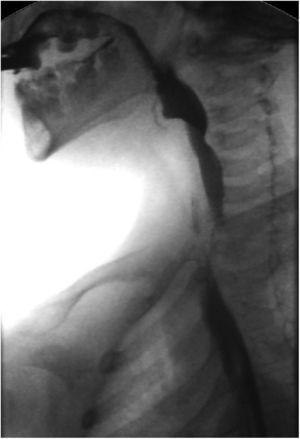

Tránsito esófago-gástrico (TEG): déficit de relajación del músculo cricofaríngeo (fig. 1)

El diagnóstico de AC es sencillo, y la técnica de elección es el TEG que demuestra la impronta del músculo cricofaríngeo a nivel del esófago cervical1–3. La manometría puede apoyar el diagnóstico, pero en muchas ocasiones es inespecífica y difícil de realizar1.